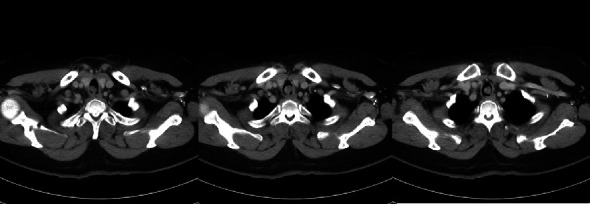

We present a rare case of tracheal schwannoma, the first reported in Hong Kong, emphasizing the diagnostic challenges and treatment outcomes. A 54-year-old woman with respiratory symptoms underwent evaluations revealing a tracheal mass causing luminal narrowing. Emergency operation with rigid bronchoscopy and cryoablation successfully removed the tumor. Follow-up bronchoscopies showed a gradual reduction in residual tumor size, with no evidence of recurrence after 3.5 years postoperation. Tracheal schwannomas are exceedingly rare, often resulting in delayed diagnosis. Clinicians should maintain a high suspicion of tracheal tumors in patients with unexplained respiratory symptoms. Spirometry and flow volume loop analysis aid in identifying upper airway obstruction. Rigid bronchoscopy is preferred for diagnosis and treatment, ensuring airway stability and obtaining tissue samples. Surgical resection remains the mainstay, but observation after endoscopic resection may be considered. This case highlights the successful management of tracheal schwannoma through endoscopic resection and cryoablation, emphasizing the need for further studies and case reports on this rare entity.

Abstract Image